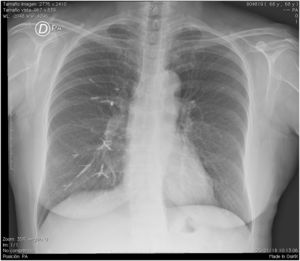

A 65-year-old female assessed for low back pain with a history of CT-guided percutaneous vertebroplasty 4 years previously secondary to vertebral fracture due to osteoporosis. As mentioned by the patient, the procedure was performed without complications and from it she achieved partial improvement of pain. On questioning she denied any respiratory symptoms. On physical examination the vital signs were normal, with 99% ambient air oxygen saturation. In the thoracic assessment the heart sounds were rhythmic, without murmurs, and the lung fields were not altered. Lumbar spine ranges of motion were diminished and there was pain on active and passive movement. Lumbar spine radiography showed scoliosis, as well as volume loss and the presence of radiopaque material at L3 (Fig. 1). Chest radiography showed the presence of radio-opaque material in right-dominant pulmonary vascular distribution (Fig. 2). Vertebral fracture is the most common complication of osteoporosis.1 In some patients vertebroplasty is used to reduce pain.2 This procedure involves the injection of cement to stabilise the anterior spine. Leakage of material has been reported in 30%–65% of patients. The risk factors described for this complication are: intravertebral fissure, cortical disruption and procedure-related factors (viscosity of the cement and volume of cement injected).3,4 It is considered that overfill of the vertebral body or inadvertent puncture into the radiated veins will facilitate the migration of cement into the perivertebral venous plexus, to pass through the hemiazygous vein, the azygous vein and flow into the inferior vena cava, which is where polymerisation of the material and embolism will occur.2 Most patients have reported asymptomatic side effects. In cases of pulmonary embolism, it has been reported that 26% will be asymptomatic5 and in <1% of cases will present some symptoms.6,7 The patient was sent to rehabilitation and treated with analgesics, with a good short-term outcome.